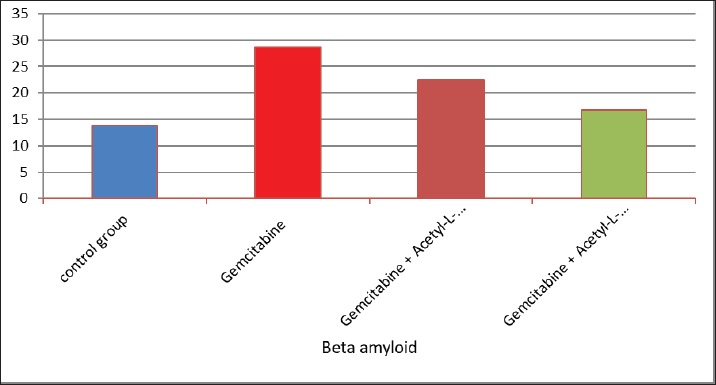

AbstractBackground: The acetyl ester of L-carnitine (ALC) is essential for cellular energy homeostasis and intermediate metabolism. It demonstrates several well-established biological characteristics, such as antioxidant activity, intracellular membrane stability, mitochondrial function improvement, and neuroprotective and neurotrophic effects. Given that oxidative stress, mitochondrial malfunction, and neuronal membrane damage have been linked to gemcitabine-induced neurotoxicity, ALC may have a preventive role against these negative consequences. Its capacity to boost mitochondrial metabolism and act as an antioxidant points to a potential mechanism for reducing damage to the central nervous system (CNS) caused by gemcitabine. Thus, using an experimental model of gemcitabine-induced neurotoxicity, we explored the possible neuroprotective benefits of ALC. Aim: This study aimed to examine the neuroprotective effects of two distinct dosages of ALC on cognitive impairment in male rats caused by gemcitabine injection. Cognitive function was assessed using well-known behavioral tests, such as the Morris water maze or novel object identification, to offer objective measures of learning and memory. This study aimed to elucidate the possible function of ALC in reducing gemcitabine-related CNS toxicity by evaluating behavioral performance in addition to biochemical indicators of oxidative stress and neuronal damage. It is anticipated that the results of this study will shed light on the dose-dependent effectiveness of ALC in maintaining cognitive function after chemotherapy. Methods: The experiment was conducted using 24 adult male rats, which were randomly assigned to four equal groups (n=6 per group). Treatments were administered once daily for 28 consecutive days. Group 1 (G1–Control): Rats received a subcutaneous injection of normal saline and served as the negative control. Group 2 (G2–Gemcitabine 25 mg/kg): Rats received 25 mg/kg of Gemcitabine intraperitoneally once daily. Group 3 (G3– ALC 50 mg/kg): Rats received 50 mg/kg of ALC intraperitoneally once daily. Group 4 (G4–Gemcitabine + ALC): Rats received a combination of Gemcitabine (25 mg/kg bw) and ALC (50 mg/kg bw), both administered intraperitoneally once daily. All treatments were administered at the same time each day to ensure consistency, and the animals were monitored throughout the study period to assess their health status and minimize stress. Results: Rats receiving ALC in addition to gemcitabine demonstrated a significant reduction in gemcitabine-induced adverse effects (p < 0.05) compared with the group treated with gemcitabine alone. This protective effect was mainly seen in characteristics associated with the function of the central nervous system, that ALC plays a neuroprotective role. Conclusion: The fourth experimental group (G4) had considerably lower levels of β-amyloid and acetylcholinesterase activity than the second (G2) and third (G3) groups. Furthermore, brain sections from the G4 group showed significantly fewer β-amyloid plaques than those from the G2 and G3 groups, according to Congo red staining histological analysis. Keywords: Acetyl-L-carnitine, Acetylcholinesterase, Beta amyloid, Congo red, Gemcitabine. IntroductionCancer treatment is frequently associated with adverse effects, as the toxicity of chemotherapeutic agents can reduce life expectancy and significantly impair patients’ quality of life. Gemcitabine is a potent cytotoxic antimetabolite that is widely used for treating various solid tumors, including pancreatic, lung, breast, and bladder cancers. Gemcitabine primarily exerts its anticancer effects by inhibiting DNA synthesis during the S phase of the cell cycle. Accurate depiction of medication indications and mechanisms of action is crucial, even though chemotherapy-induced toxicity is a significant therapeutic problem. Thus, the toxicological effects of gemcitabine administration are the main topic of this investigation, with a focus on the systemic effects (Maleki et al., 2025). White blood cell malignancies, including non-Hodgkin lymphoma, acute myeloid leukemia, also known as acute lymphocytic leukemia, and long-term myelogenous leukemia, are the main conditions treated with gemcitabine, a class of chemotherapeutic medication (Larson et al., 2024). Its effects are specific to the S-shaped cellular cycle. Significant chromosomal damage causes chromosomal abnormalities. Mitosis has the greatest effect in cells with rapid division that need to duplicate DNA (Yi et al., 2022) reactive oxygen species (ROS) are produced, and their concentrations are decreased because the function of enzymes known as antioxidants in the liver tissues is inhibited by gemcitabine. However, since this combination is known to undergo significant hepatic metabolism, the resulting increase in ROS may contribute to brain tissue injury (Tauffenberger and Magistretti, 2021). The liver, kidney, and brain all naturally produce the amino acid L- alongside the necessary amino acids methionine and lysine (Davidova et al., 2022). Since the chemical originates after flesh, its scientific designation is derived from the Latin carnus, which means meat Taub (2023). Acetyl-L-carnitine (ALC) is essential for energy utilization because it moves toxic compounds through organelles and prevents these contaminants from building up inside the cell’s tissues. It additionally carries long-chain fatty acids to the mitochondria Javan et al. (2025). ALC is essential for the oxidation of fatty acids and the conversion of energy; thus, it might safeguard the cell membranes from damage caused by oxidative stress (Kıran et al., 2023). ALC might inhibit these chemical reactions in cells by numerous pathways—preservation of mitochondrial function (Huseynova, 2025) and reduction of ROS generation at various intracellular sites (Virmani and Cirulli, 2022). Protein Kinase B is among the most common neurotransmitters in the human nervous system. Ace is a neurotransmitter used as a signaling molecule by neurons with cholinergic activity (Zulfugarova et al., 2025). The activity of cholinesterase is crucial to stop chemicals released from acetylcholine neurons from reaching the nervous system, skeletal muscle, or gland that is being activated (Ashraf, 2023). Acetylcholinesterase (AChE) quickly breaks down acetylcholine into choline and acetic acid, rendering it ineffective. The brain’s nervous system needs oxygen to function properly (Guliyeva et al., 2025). Because ace is inhibited, acetylcholine can accumulate, overstimulating cholinergic junctions and organs controlled by cholinergic neurons (Lakshmanan, 2021). Materials and MethodsIn this study, 24 male white albino rats weighing between 260 and 300 g were used. Individuals were housed in well-maintained cardboard cages that included proper ventilation, light structure, and temperature (about 30℃ ± 5℃) for 12 hours each day. The trial was conducted during a 28-day period. Twenty-four adult male rats were randomly divided into four experimental groups, each consisting of six animals. Six male rats in Group I (G1, control group) were administered intraperitoneal injections of normal saline once a day during the experiment. Six male rats in Group II (G2) received 25 mg/kg body weight of intraperitoneal gemcitabine. Six male rats in Group III (G3) were administered intraperitoneal doses of gemcitabine (25 mg/kg body weight) and ALC (50 mg/kg body weight). Six male rats in Group IV (G4) were administered gemcitabine (25 mg/kg body weight) and ALC (50 mg/kg body weight) intraperitoneally for 4 consecutive days. Blood samples were taken from each rat separately and appropriately labeled to prevent sampling bias. In compliance with institutional ethical guidelines for animal care and use, the animals were put to sleep before blood collection using a compassionate and authorized anesthetic approach instead of being exposed to chloroform. Blood was drawn via heart puncture using sterile needles in an aseptic setting after anesthesia was administered. Each animal provided approximately 5 ml of blood. The leftover blood was split into two parts, and 1 ml was set aside for whole blood analysis. After transferring approximately 2 ml into gel tubes, the mixture was left to coagulate for 30 minutes at room temperature. Study parametersMeasurement of serum β-Amyloid (Aβ₁–₄₂) A commercial rat ELISA kit (Elabscience Biotechnology Comapny Ltd., China) was used to measure serum β-amyloid (Aβ₁–₄₂) concentrations according to the manufacturer’s instructions. A quantitative sandwich enzyme immunoassay method serves as the foundation of the assay. Results were expressed in pg/ml, and the sensitivity and detection range of the kit were within the manufacturer’s limits. Every sample was examined twice to guarantee analytical precision and repeatability. Serum AChE measurementA rat AChE enzyme-linked immunosorbent assay kit (Elabscience Biotechnology Company Ltd., China) was used to test serum AChE levels in accordance with the manufacturer’s instructions. A microplate reader was used to detect the absorbance, and the standard calibration curve was used to determine the concentrations. The kit’s stated units were used to express the results. Every measurement was conducted twice, and assay performance was verified using the manufacturer’s quality control methods. Histopathological analysis (Congo red staining)Brain tissues were quickly removed and preserved for 24–48 hours following animal sacrifice in 10% neutral buffered formalin. Samples were dehydrated, cleaned, and embedded in paraffin following conventional histological methods. To find β-amyloid buildup, coronal slices (4–5 µm thick) were taken and stained with Congo red. The hippocampus and cerebral cortex, two brain areas linked to cognitive performance, were histologically examined. An investigator who was blinded to the experimental groups examined the amyloid deposits under light microscopy. Statistical analysisSPSS software (version 24.0; IBM Corp., USA) was used to analyze the data. Every outcome is presented as mean ± standard error. One-way analysis of variance was used to compare the various experimental groups. When a statistically significant difference was found, Tukey’s test was used in post-hoc multiple comparison analysis to find differences between individual groups. A statistically significant p-value was defined as <0.05. Ethical approvalThis work was approved by the ethics committee of the College of Veterinary Medicine, Kerbala University (UOK.VET. PH.2025). ResultsThe results of the present investigation indicate that the Gemcitabine group had a significant (p ≤ 0.05) raised level of blood samples beta-amyloid when compared with the remainder of the categories, whereas the Gemcitabine + ALC (25 mg/kg/bw) group showed a significant (p ≤ 0.05) improve when contrasted to the comparison group and the combination of Gemcitabine + ALC (300 mg/kg/bw) organization. However, Fig. 1 shows that there was no statistically significant difference (p > 0.05) in serum-amyloid levels between the control group and the group treated with gemcitabine + ALC (300 mg/kg bw). The present research also demonstrates that the Gemcitabine category had a significant (p ≤ 0.05) improvement in blood samples AChE when compared with each of the remaining organizations, whereas the gemcitabine + ALC (25 mg/kg/bw) category showed an important (p ≤ 0.05) increase when compared with the group that received no treatment and the gemcitabine + ALC (300 mg/kg/bw) organization (Fig. 1).

Fig. 1. Effect of gemcitabine, gemcitabine + ALC (25 mg/kg/bw), and gemcitabine + acetyl-L-incarnadine (300 mg/kg/bw) on serum beta-amyloid levels. The present research also demonstrates that the Gemcitabine category had a significant (p ≤ 0.05) improvement in blood samples AChE when compared with each of the remaining organizations, whereas the gemcitabine + ALC (25 mg/kg/bw) category showed an important (p ≤ 0.05) increase when compared with the group that received no treatment and the gemcitabine + ALC (300 mg/kg/bw) organization (Fig. 2).